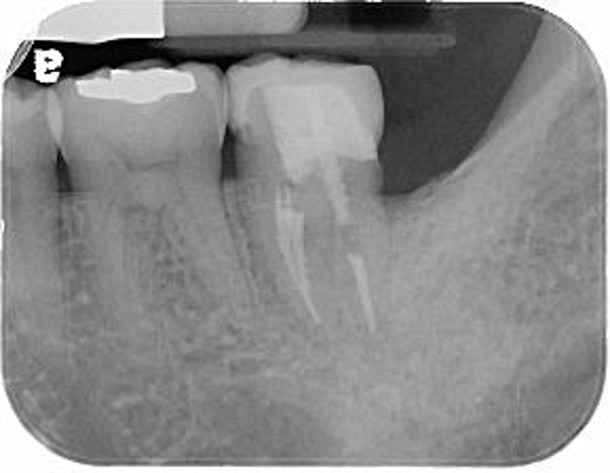

膺復前評估陶瓷斷裂處